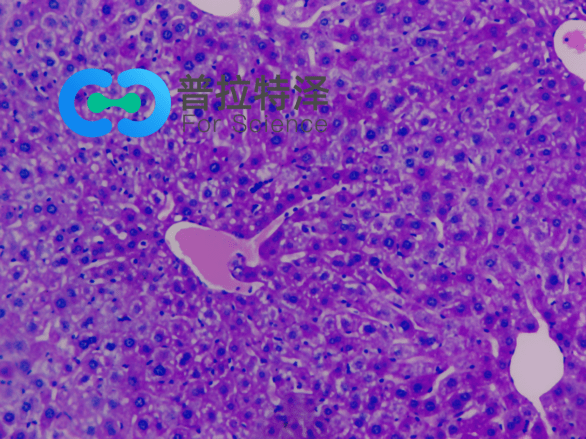

PAS染色實(shí)驗(yàn)過(guò)程中常見(jiàn)問(wèn)題解答由普拉特澤生物為大家總結(jié)分享。PAS染色作為一種在組織學(xué)中廣泛應(yīng)用的染色技術(shù),雖然具有高度的特異性和敏感性,但在實(shí)際操作過(guò)程中,也常會(huì)遇到一些問(wèn)題和挑戰(zhàn)。本文是關(guān)于PAS染色實(shí)驗(yàn)的最后一篇介紹,前面我們學(xué)習(xí)了PAS染色實(shí)驗(yàn)材料有哪些?、PAS染色和mpo染色區(qū)別是什么?、PAS染色實(shí)驗(yàn)注意事項(xiàng)以及PAS染色臨床應(yīng)用,可以點(diǎn)擊標(biāo)題直接傳送回去學(xué)習(xí)的哦。普拉特澤生物組織染色檢測(cè)平臺(tái)承接酵母雙雜實(shí)驗(yàn)外包上百例,早就為大家把實(shí)驗(yàn)過(guò)程中要踩的雷、吃的虧幫大家吃完了,現(xiàn)在我們就來(lái)看看,PAS染色中常見(jiàn)問(wèn)題的解答:

綜上所述,PAS染色雖然是一種常用的組織學(xué)染色方法,但在實(shí)際操作中常常會(huì)遇到一些問(wèn)題。通過(guò)掌握常見(jiàn)問(wèn)題及其解決方法,我們可以更好地應(yīng)用這項(xiàng)技術(shù),提高染色效果和觀察結(jié)果的準(zhǔn)確性。同時(shí),不斷學(xué)習(xí)和實(shí)踐也是提高PAS染色技術(shù)水平的重要途徑。